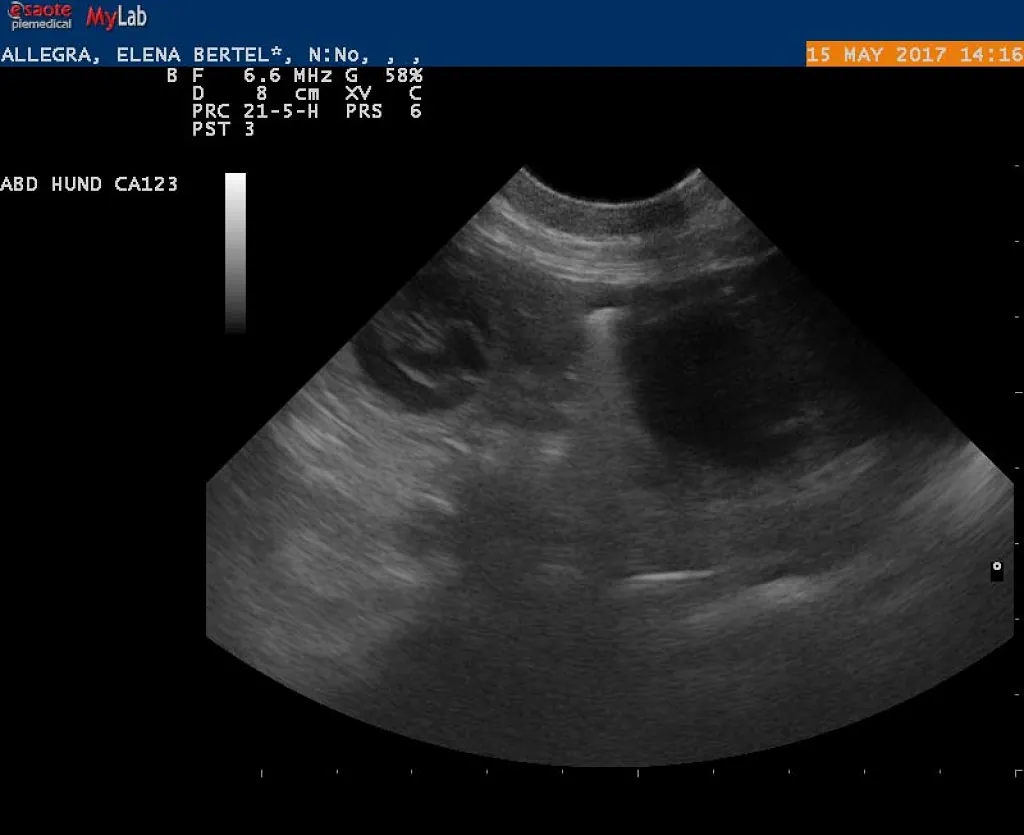

15.05.2017

Alice er drægtig!

e-kuld, 2017, sommer, kennel basta dog, schnauzere, schnauzerhvalpe, schnauzeropdræt, mellemschnauzer, alenzo, alice, hvalpe, købe schnauzer

Dejlig, dejlig nyhed!!!

Alice (Allegra)  er drægtig!

Scanning i dag har nemlig bekræftet den dejlige nyhed!

Hvor mange hvalpe er der inde? Tja, en del af dem kan du se på de billeder fra scanning :)

Nu krydser vi fingre for at alt går godt og vi får dejlige hvalpe efter de smukke og dygtige forældre!

P.S. Scaninngsbillederne ved klik på dem vil kunne ses i større størelse!